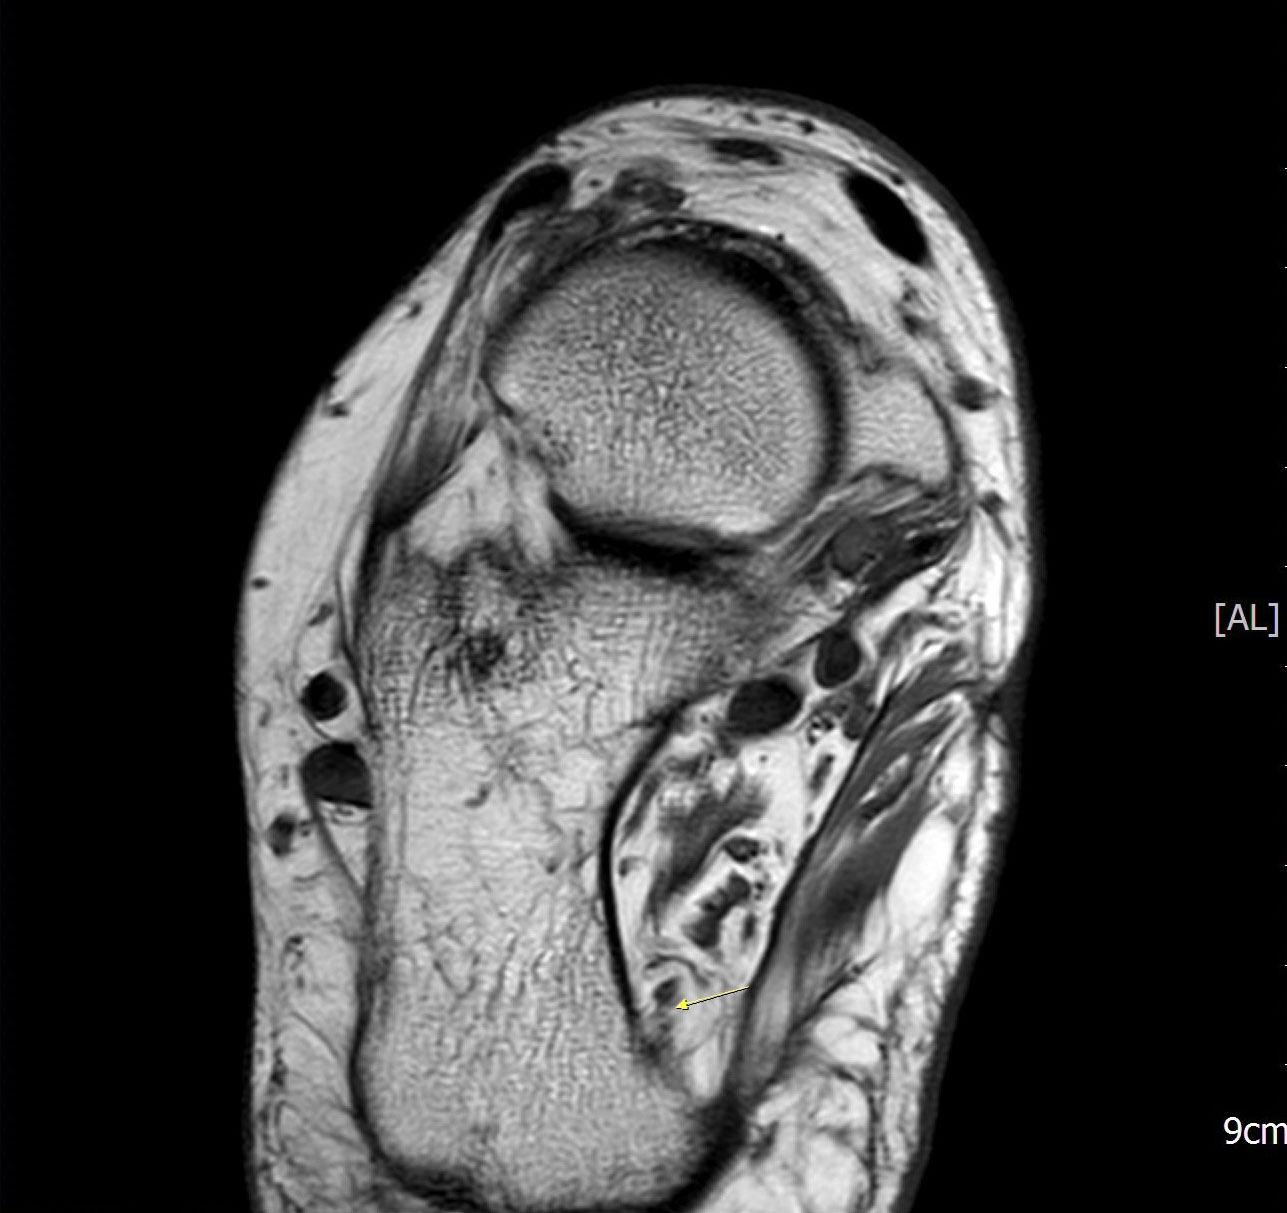

Abbildung 1: Plantarer und dorsaler Sporn im Röntgenbild und im MRT

Abb. 1a und Abb. 1b: großer dorsaler Fersensporn und ein minimaler plantarer Sporn, Patient, 50 Jahre.

Abb. 1c: Bild eines isolierten großen plantaren Fersensporns. Patientin, 32 Jahre.

Zum Lesen der Bildbeschreibung und zur Vollansicht bitte die Bilder anklicken. Bilder: Manfred Thomas.